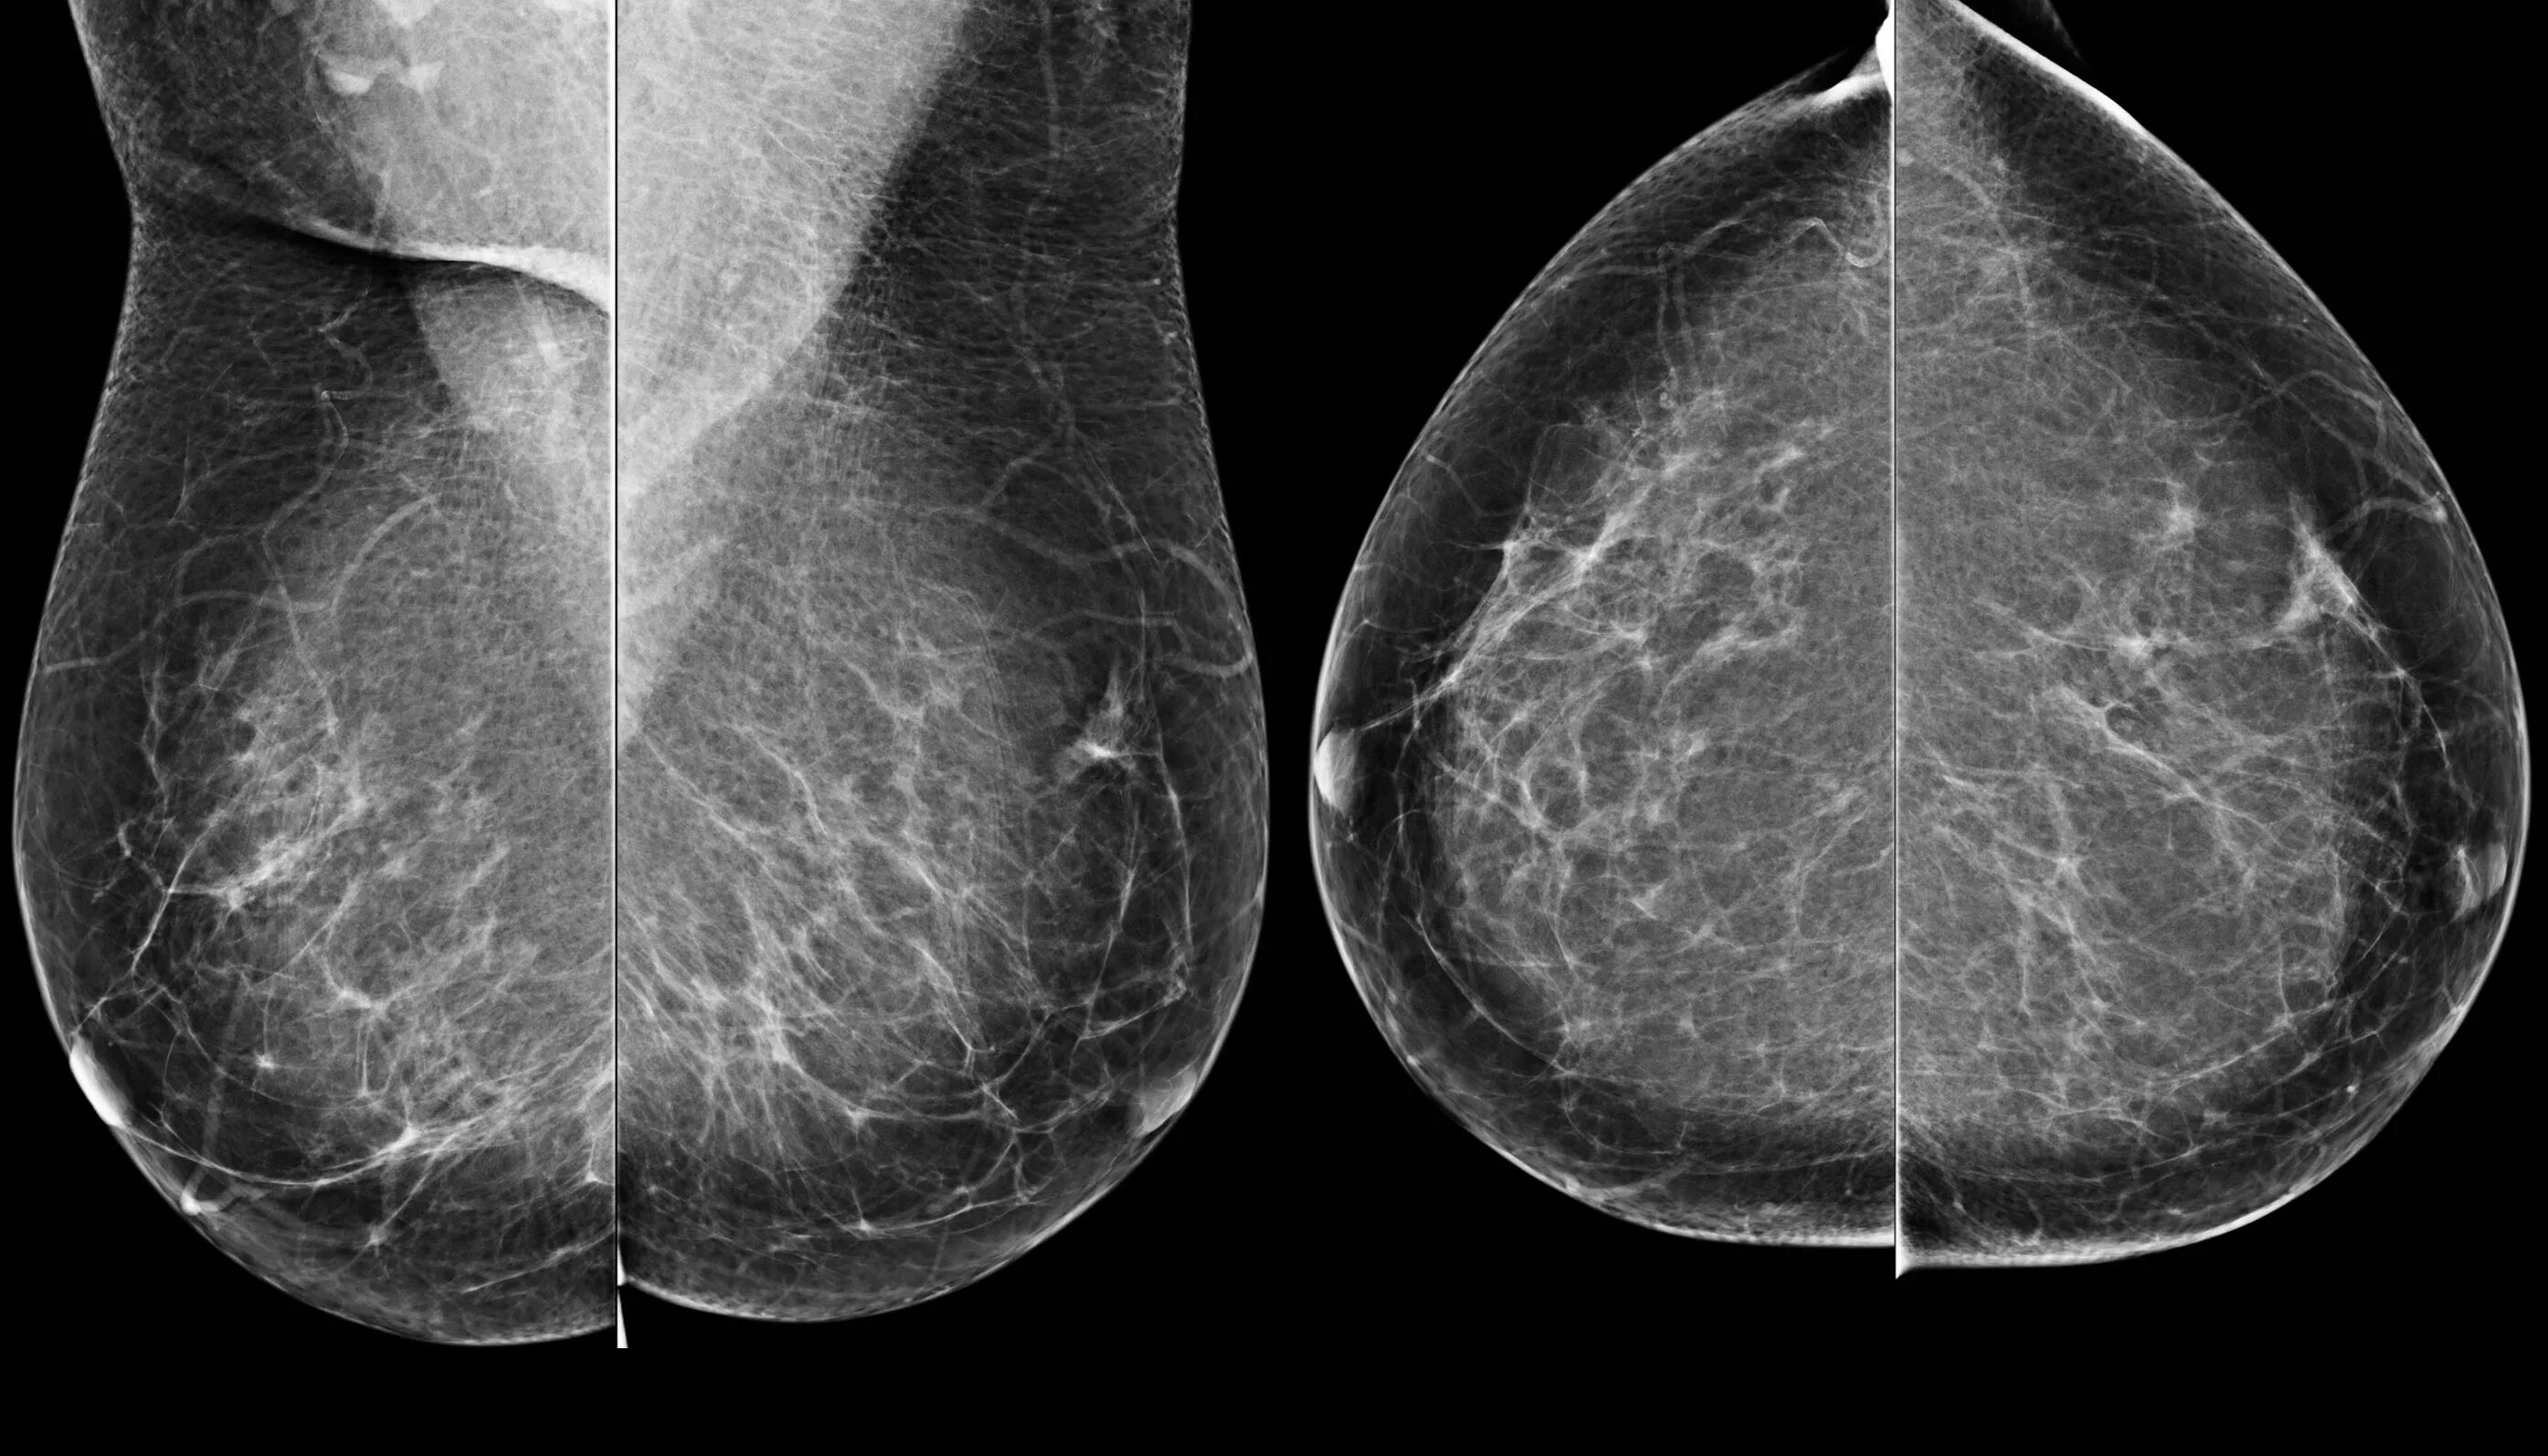

Фиброз грудных